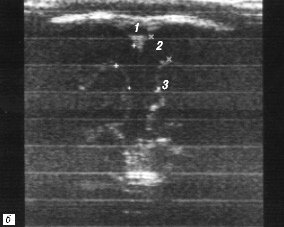

Рис. 6. Измерение ширины субарахноидального пространства и ширины межполушарной щели на одном-двух корональных срезах - схема (а) и эхограмма мозга (б).

1 - верхний сагиттальный синус;

2 - ширина субарахноидального пространства;

3 - ширина межполушарной щели;

4 - серп мозга.